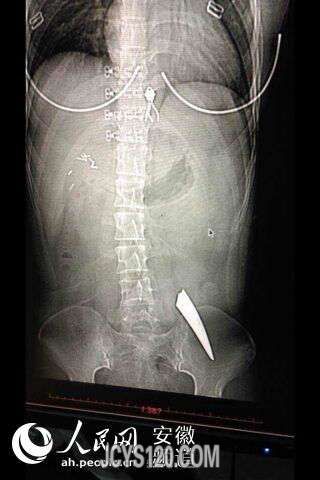

5月24日7点左右,安徽安庆市立医院妇产科,一名女护士被病人捅伤。 人民网安徽频道记者从该医院了解到,受伤的护士姓许,30多岁。行凶者为一名女患者。 据了解,行凶者行凶后,尖刀断裂,有13厘 ... 阅读全文>